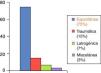

Su etiología es variable: espontánea, traumática, iatrogénica. A día de hoy la más frecuente es de origen idiopático o espontáneo (fig. 3). La clínica es poco específica, pero conjuntamente con los factores de riesgo nos ayudará ante la sospecha de dicho cuadro. Así puede cursar con: dolor abdominal y/o torácico, cuadros isquémicos a diferente niveles, y en un porcentaje nada desdeñable, el cuadro clínico es asintomático (17%)2 (fig. 4). El diagnóstico de confirmación se realiza en más de la mitad de los casos mediante angio-TAC (75%), aunque también se puede realizar a través de estudios ecográficos, angiográficos o con angio-RM5.